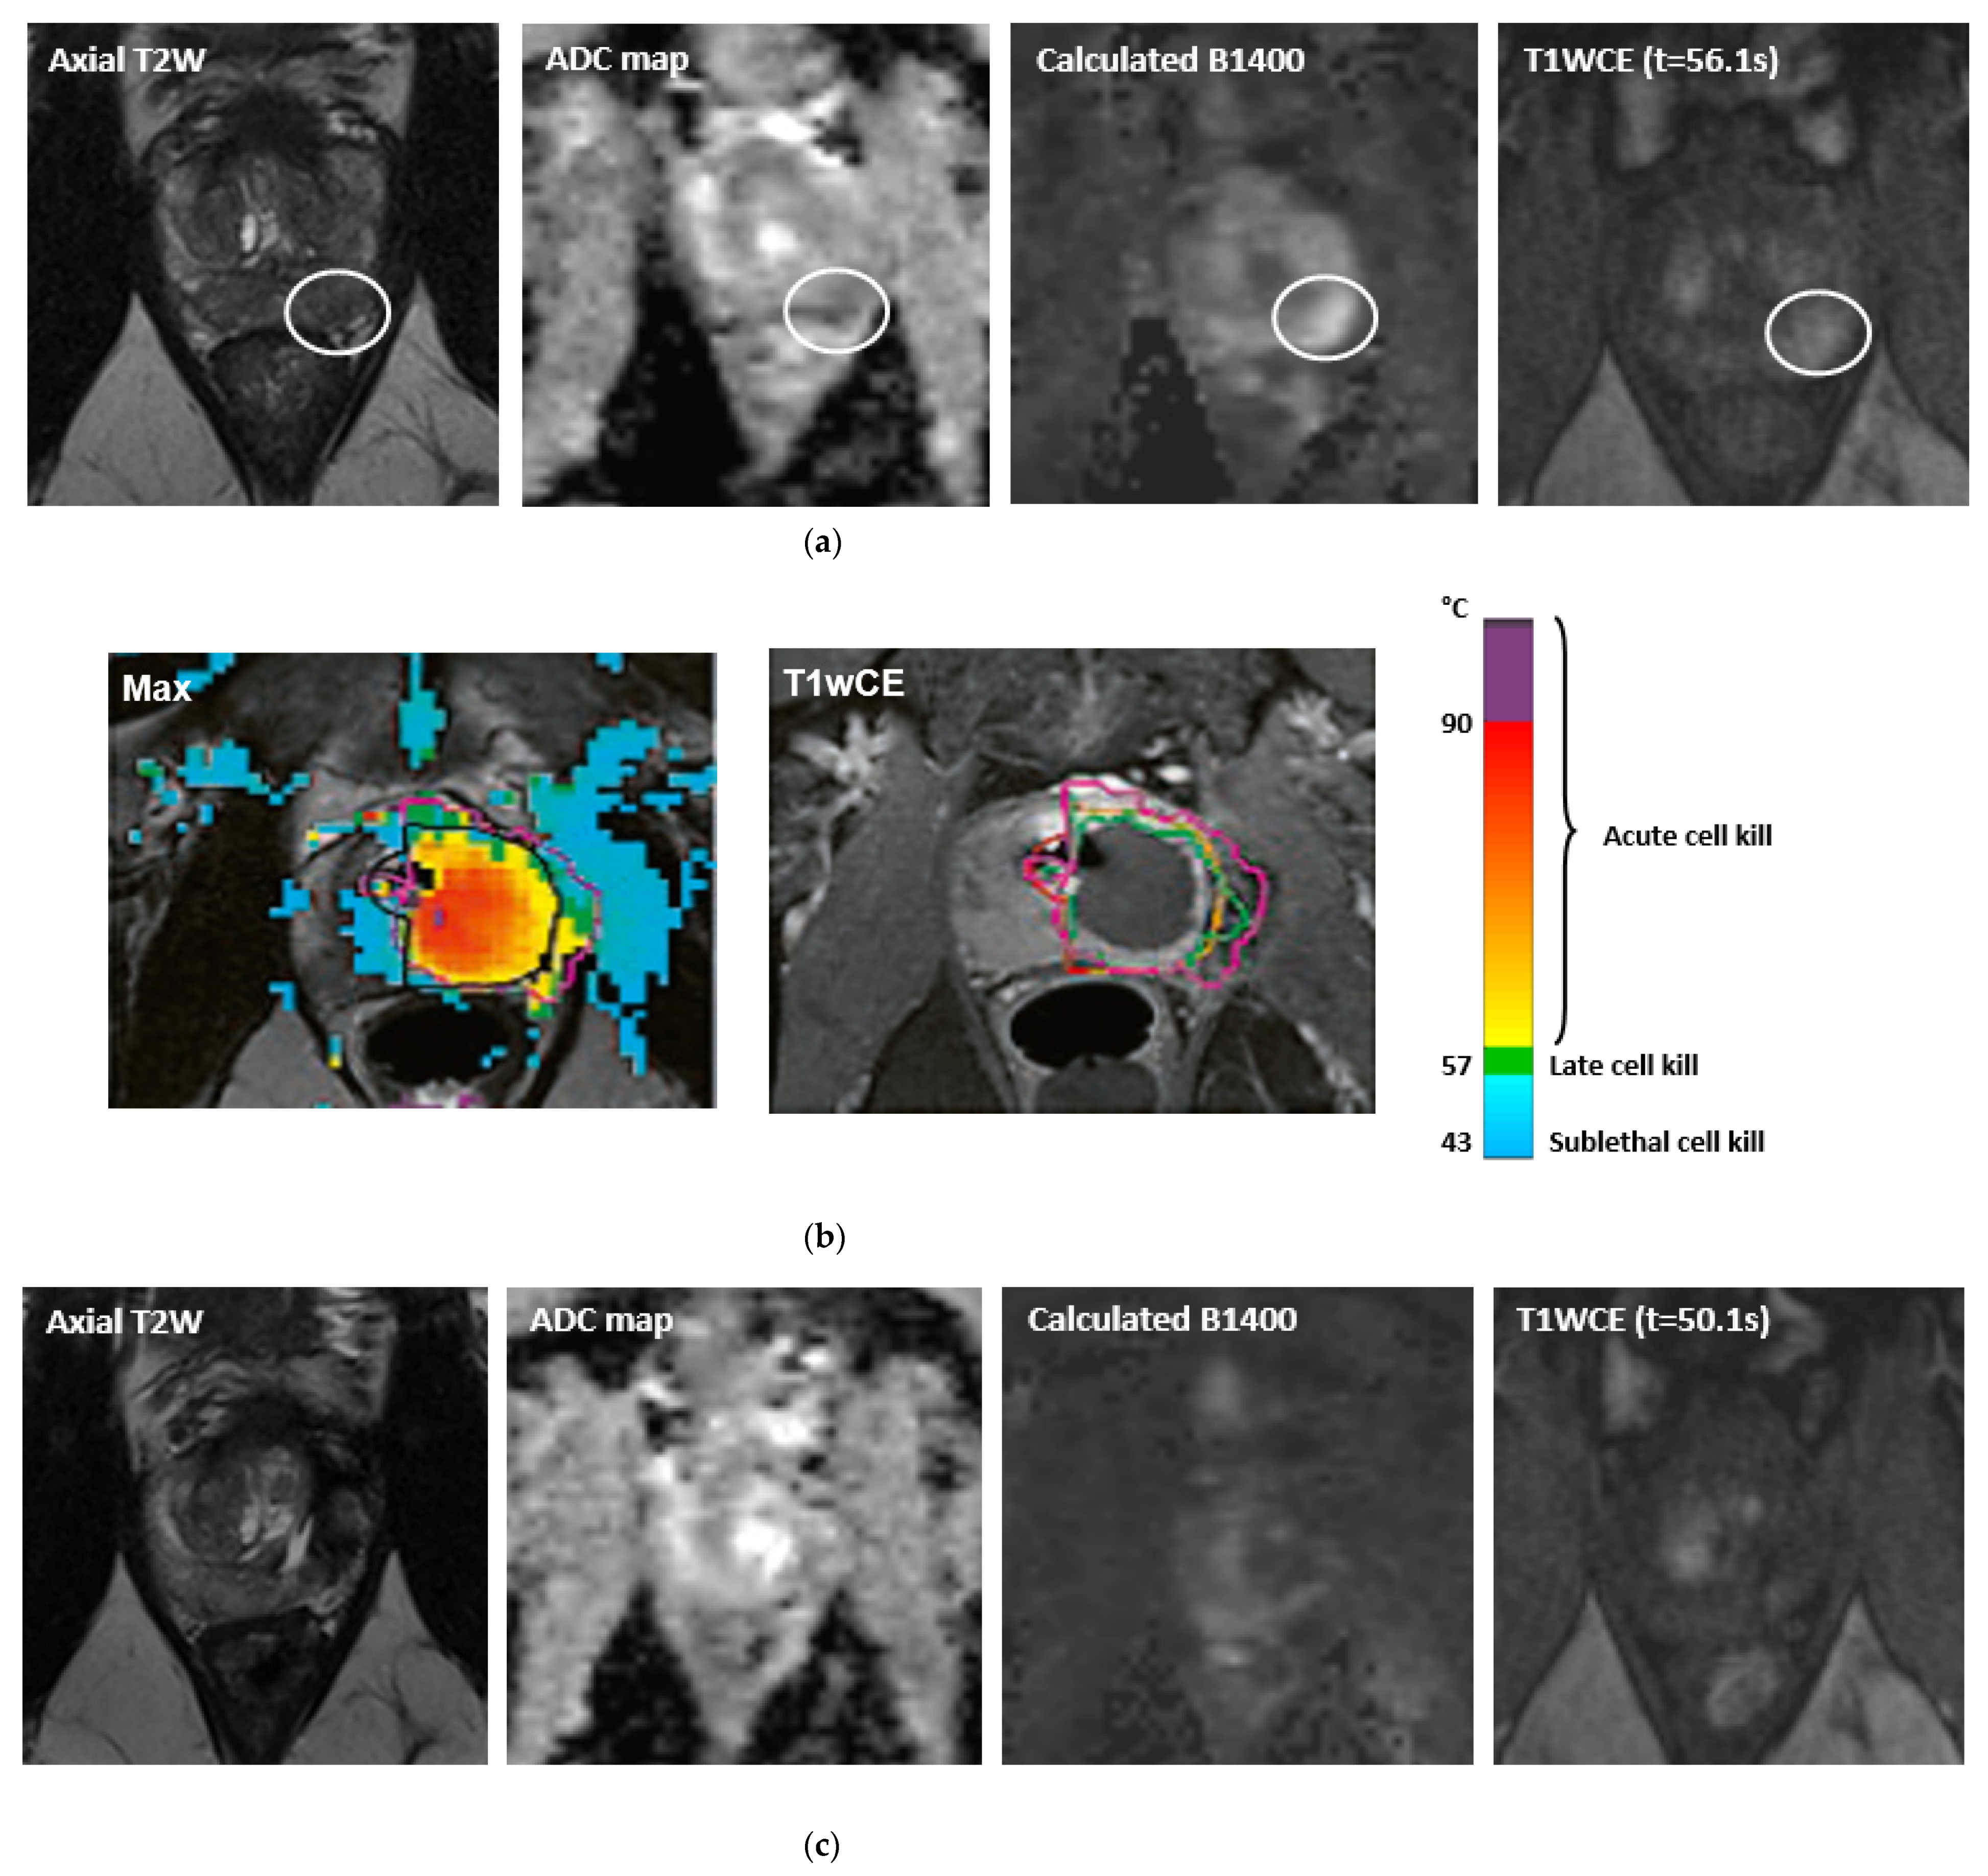

- Ramsay, E.; Mougenot, C.; Staruch, R.; Boyes, A.; Kazem, M.; Bronskill, M.; Foster, H.; Sugar, L.; Haider, M.; Klotz, L.; et al. Evaluation of Focal Ablation of Magnetic Resonance Imaging Defined Prostate Cancer Using Magnetic Resonance Imaging Controlled Transurethral Ultrasound Therapy with Prostatectomy as the Reference Standard. J. Urol. 2017, 197, 255–261. [Google Scholar] [CrossRef]

- Anttinen, M.; Mäkelä, P.; Suomi, V.; Kiviniemi, A.; Saunavaara, J.; Sainio, T.; Horte, A.; Eklund, L.; Taimen, P.; Sequeiros, R.B.; et al. Feasibility of MRI-guided transurethral ultrasound for lesion-targeted ablation of prostate cancer. Scand. J. Urol. 2019, 53, 295–302. [Google Scholar] [CrossRef]

- Anttinen, M.; Mäkelä, P.; Viitala, A.; Nurminen, P.; Suomi, V.; Sainio, T.; Saunavaara, J.; Taimen, P.; Sequeiros, R.B.; Boström, P.J. Salvage Magnetic Resonance Imaging–guided Transurethral Ultrasound Ablation for Localized Radiorecurrent Prostate Cancer: 12-Month Functional and Oncological Results. Eur. Urol. Open Sci. 2020, 22, 79–87. [Google Scholar] [CrossRef]

- Chopra, R.; Burtnyk, M.; N’Djin, W.A.; Bronskill, M. MRI-controlled transurethral ultrasound therapy for localised prostate cancer. Int. J. Hyperth. 2010, 26, 804–821. [Google Scholar] [CrossRef]

- Chopra, R.; Colquhoun, A.; Burtnyk, M.; N’Djin, W.A.; Kobelevskiy, I.; Boyes, A.; Siddiqui, K.; Foster, H.; Sugar, L.; Haider, M.A.; et al. MR Imaging–controlled Transurethral Ultrasound Therapy for Conformal Treatment of Prostate Tissue: Initial Feasibility in Humans. Radiology 2012, 265, 303–313. [Google Scholar] [CrossRef]

- Chin, J.L.; Billia, M.; Relle, J.; Roethke, M.C.; Popeneciu, I.V.; Kuru, T.H.; Hatiboglu, G.; Mueller-Wolf, M.B.; Motsch, J.; Romagnoli, C.; et al. Magnetic Resonance Imaging–Guided Transurethral Ultrasound Ablation of Prostate Tissue in Patients with Localized Prostate Cancer: A Prospective Phase 1 Clinical Trial. Eur. Urol. 2016, 70, 447–455. [Google Scholar] [CrossRef]

- Nair, S.M.; Hatiboglu, G.; Relle, J.; Hetou, K.; Hafron, J.; Harle, C.; Kassam, Z.; Staruch, R.; Burtnyk, M.; Bonekamp, D.; et al. Magnetic resonance imaging-guided transurethral ultrasound ablation in patients with localised prostate cancer: 3-year outcomes of a prospective Phase I study. Br. J. Urol. 2020, 127, 544–552. [Google Scholar] [CrossRef]

- Klotz, L.; Pavlovich, C.P.; Chin, J.; Hatiboglu, G.; Koch, M.; Penson, D.; Raman, S.; Oto, A.; Fütterer, J.; Serrallach, M.; et al. Magnetic Resonance Imaging-Guided Transurethral Ultrasound Ablation of Prostate Cancer. J. Urol. 2021, 205, 769–779. [Google Scholar] [CrossRef]